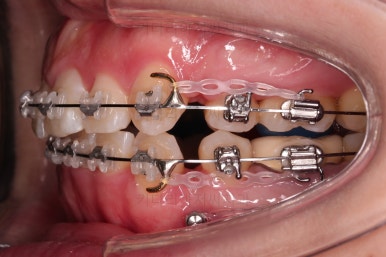

밀고 당기기를 조절하기 위해서 미니스크류도 사용합니다.

이 뽑은 공간을 자연스럽게 줄여 나갑니다.

지금부터는 입이 안들어가도록 주의하며 남은 자리를 모으고 교합을 맞춰줍니다.

오히려 이 때 부터가 훨씬 어려운 과정입니다.

미니스크류를 적절히 이용해서 어금니를 앞으로 당겨주기도 하면서 입매를 유지하며 교합을 맞춰줍니다.